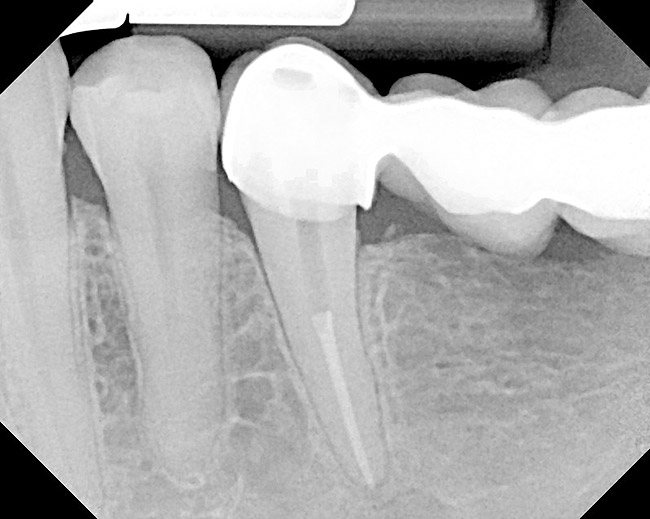

Figure 18  Radiographic examination after smoothing and blending of the bony surfaces confirmed that the bone was smooth and the ledge was eliminated.

Figure 18

Figure 22  Radiograph taken 8 weeks after closed-flap resective surgery was performed. Note that the bony contour was good, but some minor unevenness was apparent.

Figure 22

Figure 23  Radiograph taken 6 months after resective surgery and placement of the definitive prosthesis. Note how the bony crest remodeled and was much smoother than seen in the 8-week postoperative radiograph. By making the surgical correction using the closed-flap technique at the time of preparation and impression taking, a significant amount of operative time (> 6 months) was saved and an excellent biologic result was achieved.

Figure 23